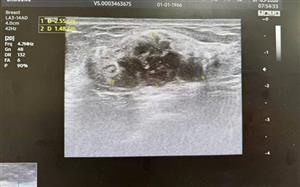

Phát hiện ung thư vú khi cơ thể vẫn "khỏe mạnh": Chuyên gia khuyến cáo tầm quan trọng của tầm soát sớm.

“Ăn ngủ bình thường, không đau nhức, không sờ thấy khối u thì chắc chắn cơ thể không có bệnh” - đó là một niềm tin vô hình tạo nên một tâm lý trì hoãn đầy rủi ro trong suy nghĩ của hàng triệu phụ nữ Việt Nam.